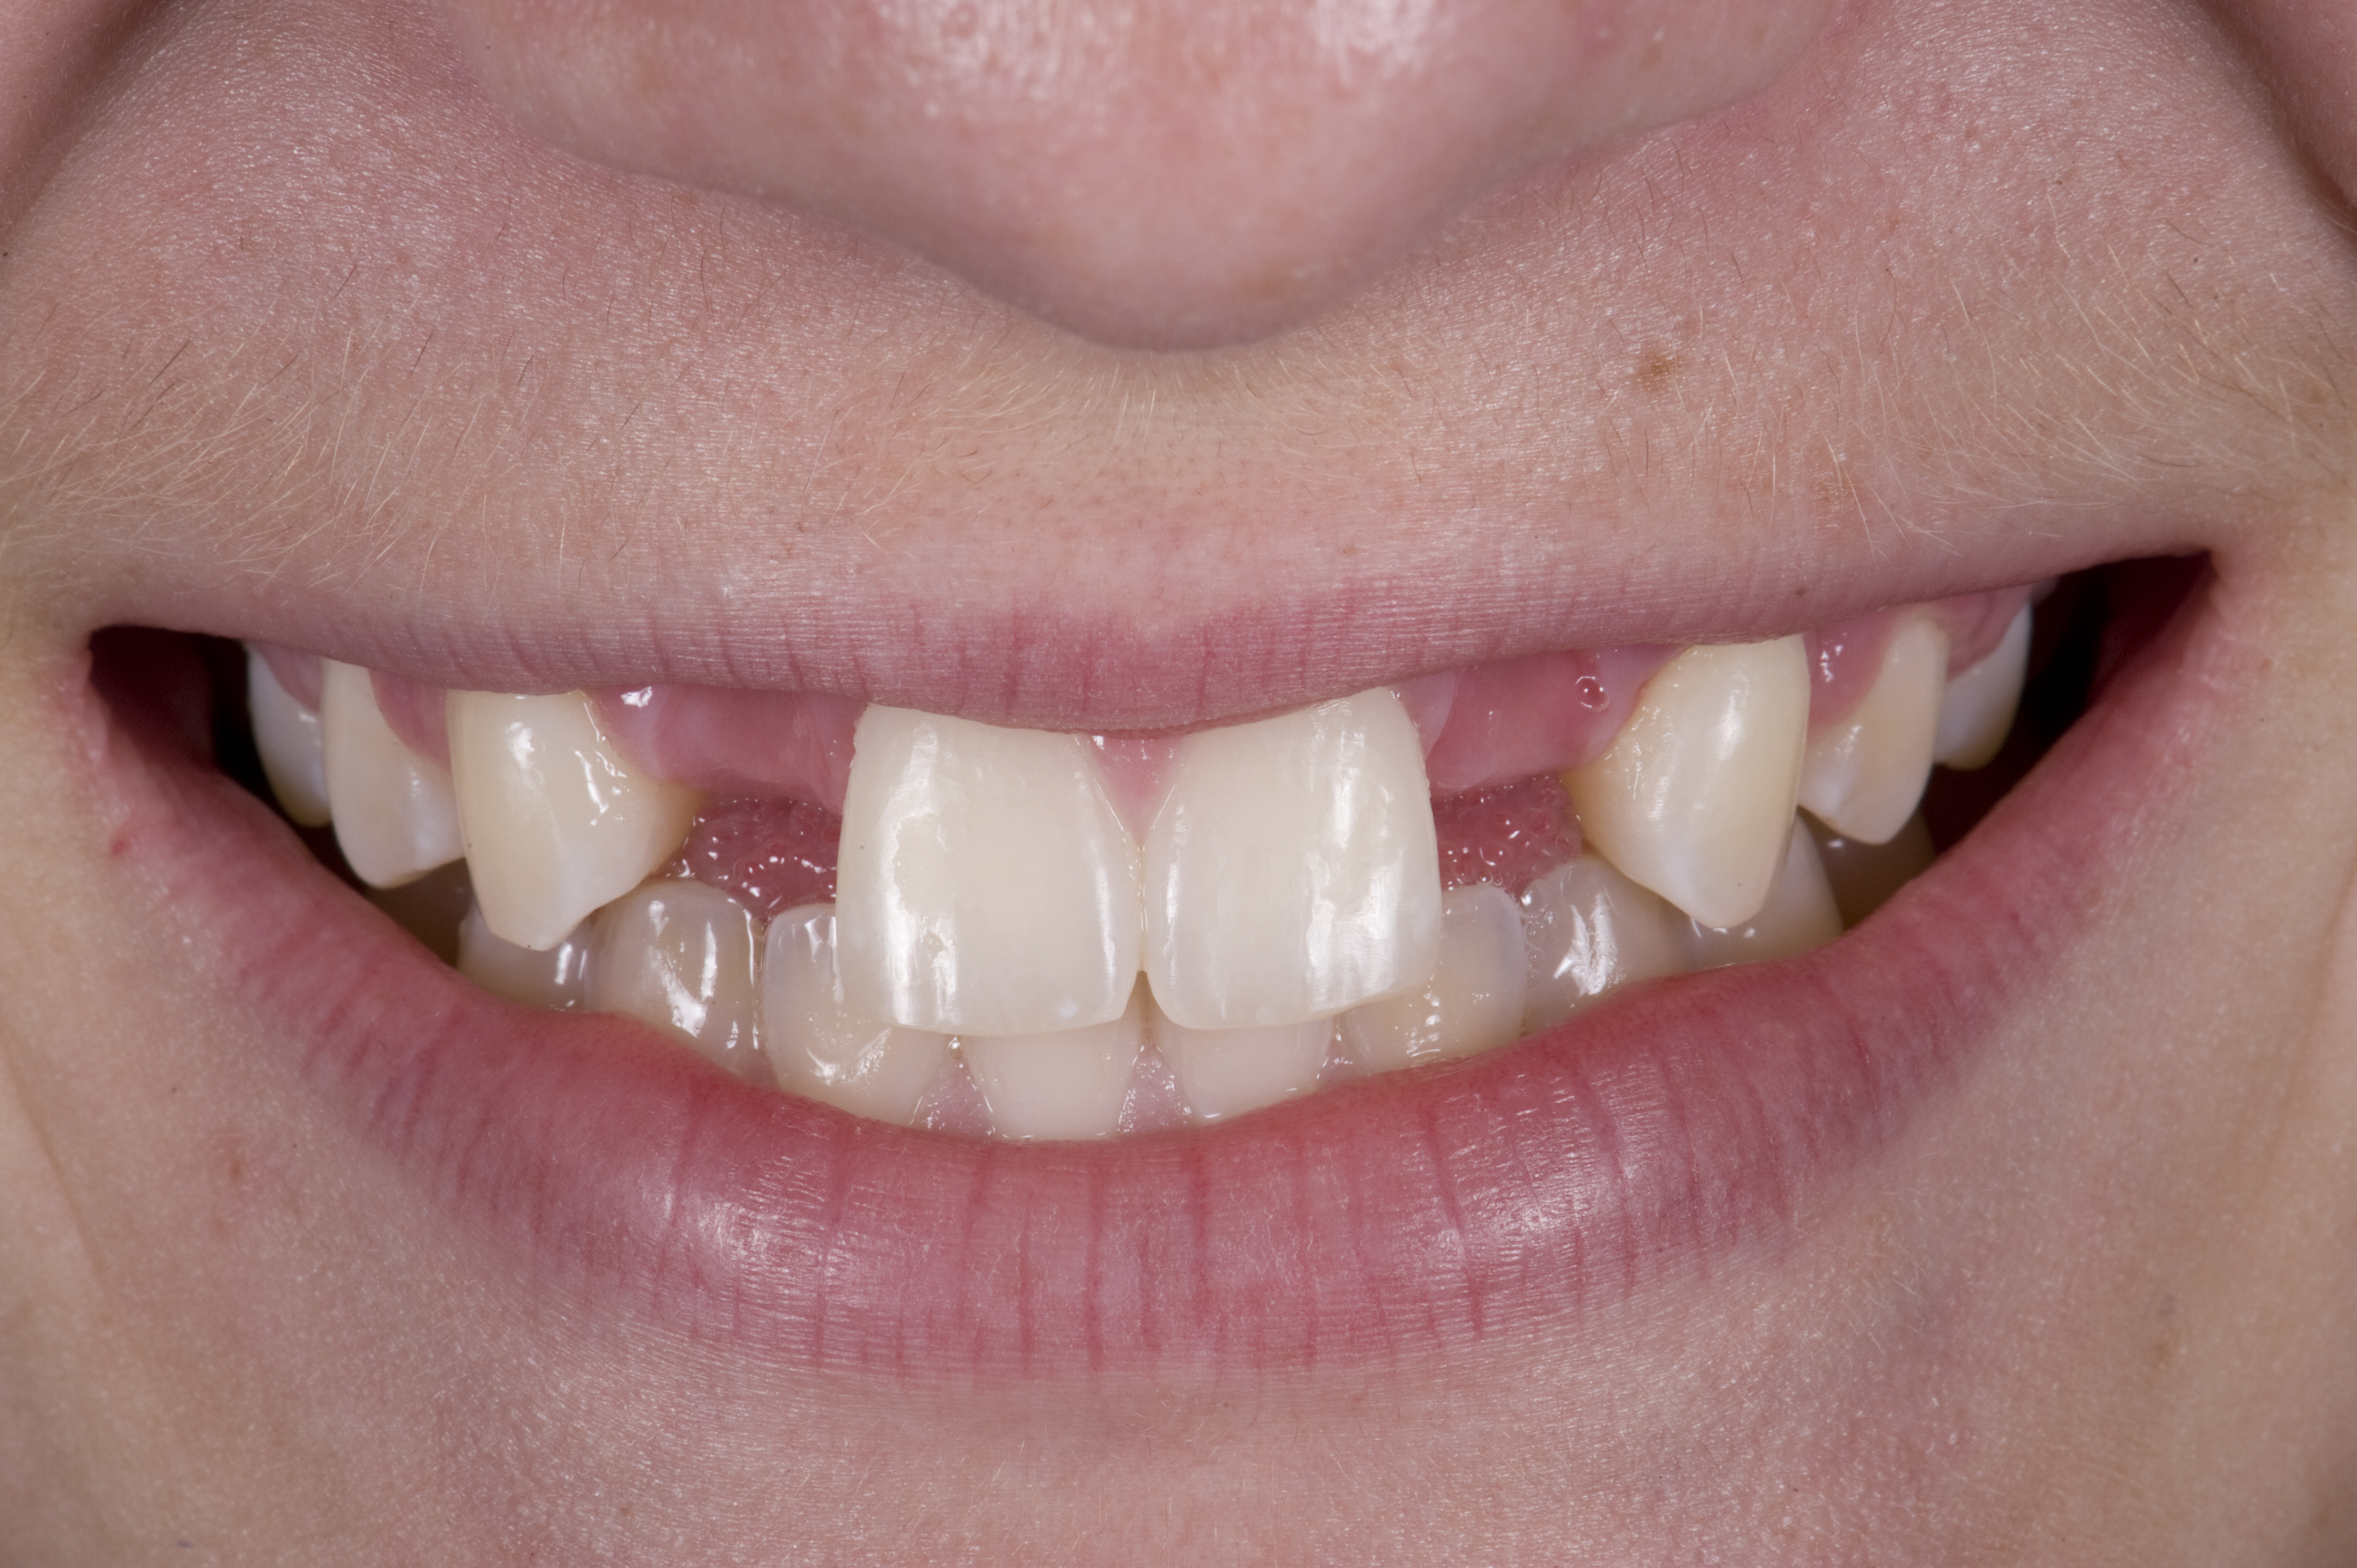

(12.) 15-year-old girl after orthodontic therapy idealized maxillary lateral incisor spaces.

Figure 12

(13.) Deficient ridges in the areas of the missing lateral incisors.

Figure 13

(14.) Occlusal view. Some form of augmentation would be needed if implants were being considered.

Figure 14

Case Presentation 2: Patient Does Not Want to Have an Implant Placed

Some patients do not want an implant due to the need for surgical intervention, and others may not have enough space for implant placement. A 15-year-old patient presented to the office after completion of orthodontic treatment to idealize the spacing of her teeth and improve her occlusal relationship (Figure 12 through Figure 14). Because both of her maxillary lateral incisors were missing, the patient was wearing a retainer with lateral incisor pontics. She had a busy school schedule, but expressed her desire for a fixed restorative option. All of her options were discussed, and the patient was informed that if she wanted an implant, she would have to wait for at least 3 to 4 years for completion of growth. The patient was not sure if or when she wanted to have an implant placed in the future, especially considering her busy schedule and desire to attend college after high school. Considering her age and the need to be conservative, a single-wing zirconia Maryland Bridge was chosen as the ideal prosthetic replacement option. Because bonding a non-etchable and smooth surface such as zirconia requires chemical adhesion, it was decided to use a modified technique to make the bridge more retentive. One of the ways to improve adhesion of a zirconia bridge is to use an etchable feldspathic ceramic layer on the internal surface of the zirconia retainer.56-58 Unfortunately, it can be difficult to determine the thickness of the ceramic and ensure accurate seating of the restoration.